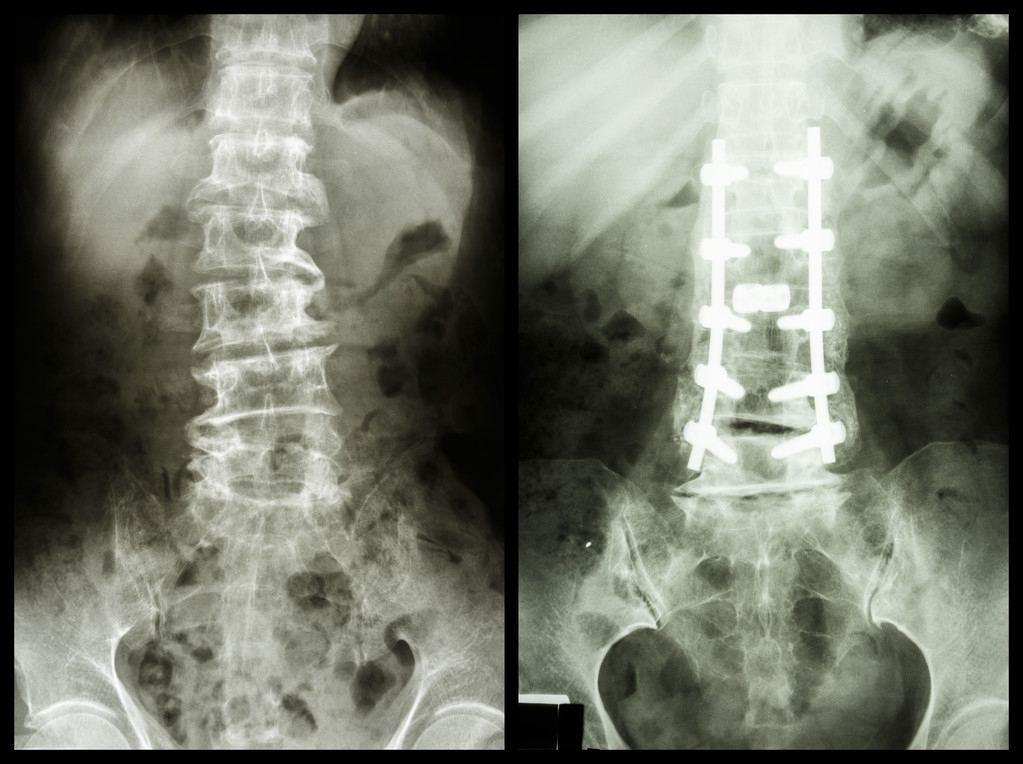

引起*泄早**的器质性因素正在探讨中,有人认为脊髓系统疾病如多发性硬化症或脊髓肿瘤、癫痫发作或大脑皮层器质性病变如脑血管意外,可引起射精失控。也有报告提示糖尿病、心血管疾病、骨盆骨折、泌尿生殖系统疾病如尿道炎、前列腺炎、精囊炎以及前列腺增生等,均与*泄早**相关。